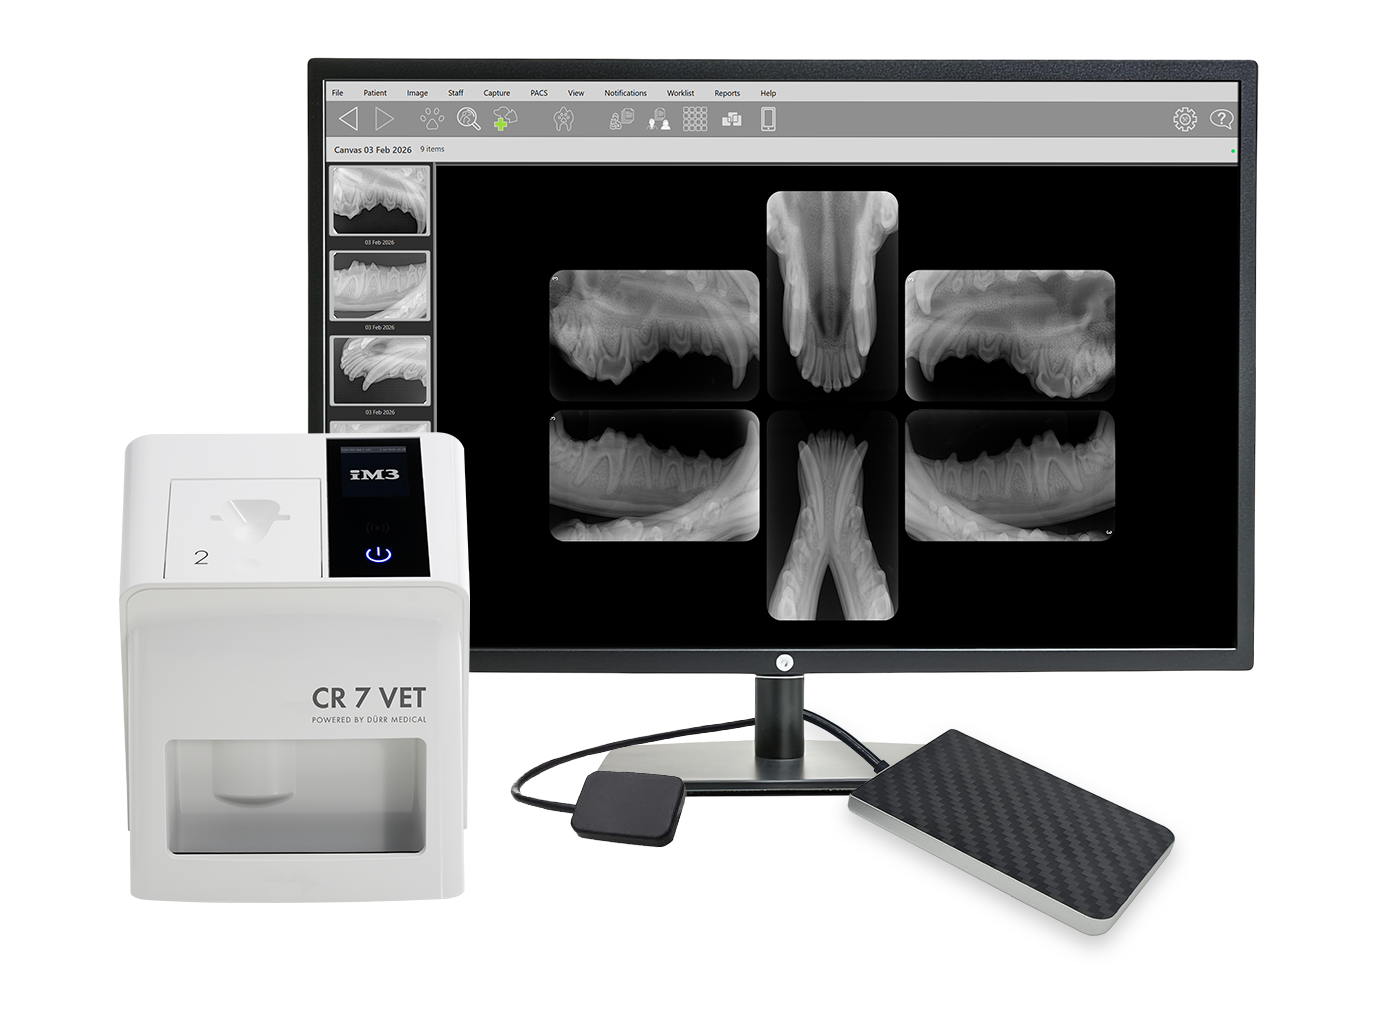

Compatibilidad universal con sistemas de imagen dental

Conecte prácticamente cualquier sensor o lector dental CR o DR mediante un controlador TWAIN estándar. Utilice los sensores existentes junto con los nuevos productos de imagen iM3 en un único sistema, lo que permite emplear sensores de mayor formato para reducir el número de imágenes, la exposición a la radiación y el tiempo de captura sin necesidad de sustituir el hardware heredado.